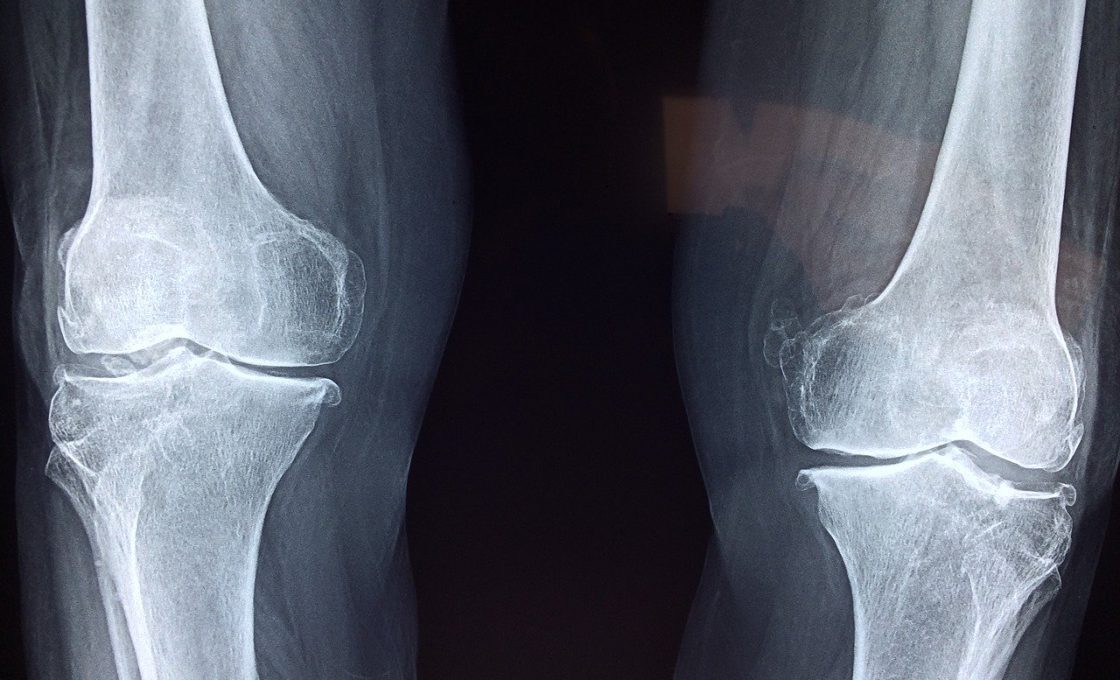

reconstruction ligament anterieur